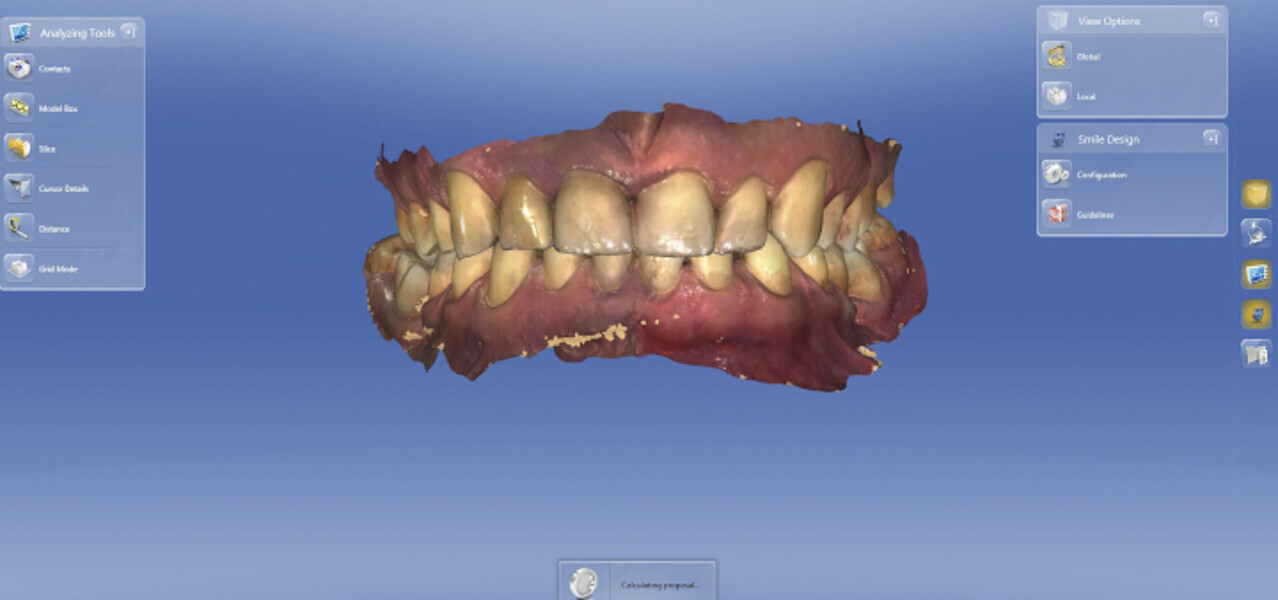

Fig. 3: Buccal scan: information on the positioning of the maxilla relative to the mandible. This is absolutely necessary for designing a crown.

Fig. 4: Designing the guide in the Simplant software based on the planned implant position.